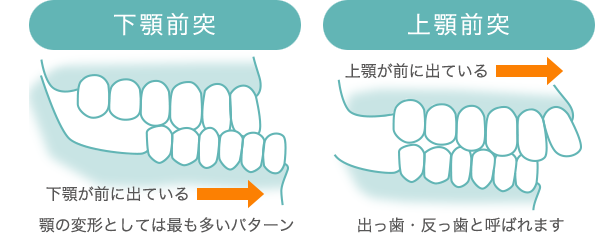

受け口(下顎前突)の症状に度合いはあるのか

顎変形症とは?